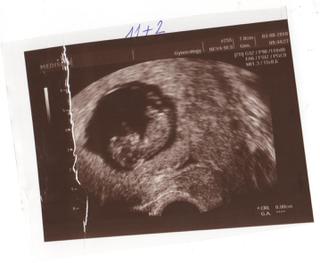

lehe-jééé,to je krásnej drobeček.skvělé,že je všechno ok.tak jen tak dál. 🙂

@leheckova krásná fotečka, moc gratuluju a opatrujte se oba!!!

LEHE moc gratuluju krasna fotecka 🙂 🙂 🙂 🙂 🙂 🙂 🙂